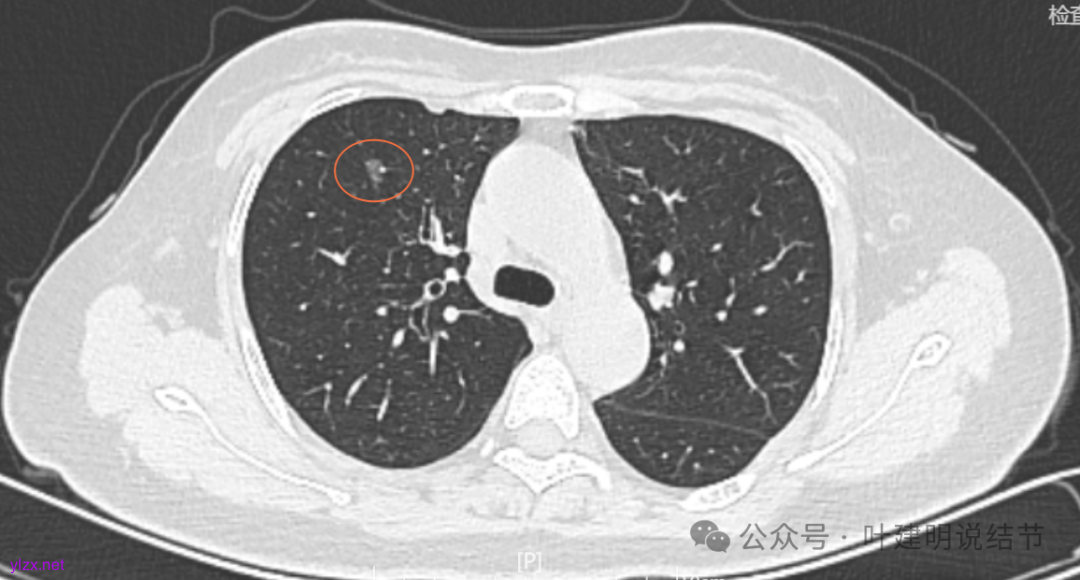

7.2022年11月1日B医院复查ct,显示肺结节0.89*0.51cm。其余变化不大。

8.2023年1月B医院复查ct,显示最大肺结节0.85*0.73cm,其余变化不大。

9.2023年4月复查ct,显示最大肺结节0.79*0.72。2023年3月短暂去某地疗养一月。

10.2023年11月28日复查CT,显示最大结节0.8*0.7cm。

11.2024年9月复查,显示最大结节0.81*0.72。

12.2025年4月复查,显示最大结节0.9*0.7。 另外,看几次报告,多发磨玻璃结节数量在上升,从2022年的3个到2025年的7个。

我们发现其实各病灶与三年前比说不上显著进展。

两肺多发磨玻璃结节,主病灶混合密度且有小血管进入,表面不平有毛刺,考虑微浸润性腺癌或浸润性腺癌可能性大,其余部分考虑原位癌或微浸润性腺癌,部分考虑肺泡上皮增生或不典型增生可能。总体上对比2022年说不上太明显的进展。但对于是否手术来讲,我仍倾向当年的意见,左侧的可以考虑近期亚肺叶(个人倾向楔切)切除,右侧的先随访,以后有进展并风险增加再考虑干预处理。因为要拉长两次手术的间隔,这样对机体的创伤与恢复更加有利一些。若定要仍不开刀,则建议要4-6个月复查,不过个人不太主张过于保守随访,对于像主病灶这种有少许实性成分的,不能保证肯定安全。意见供参考!